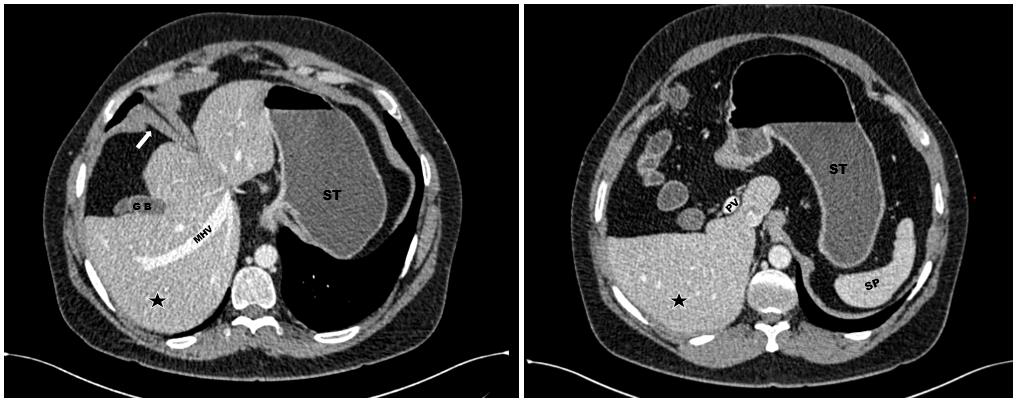

had reported bilateral renal calculi. A contrast-enhanced CT (CECT)

of the abdomen was advised for further evaluation. The CT study

demonstrated a malrotated liver with the hepatic hilum oriented

anterolaterally and the gallbladder located in an atypical anterior

position [Figure 1] There was moderate to marked elevation of the

Figure 1:Axial CECT abdomen demonstrates a malrotated liver with the

hepatic hilum directed antero-laterally and the gallbladder oriented anteriorly.

A thickened anterior diaphragmatic slip is noted (white arrow). The stomach

and spleen are in their normal positions. GB – Gallbladder; MHV – Middle

hepatic vein; ST – Stomach; SP – Spleen; ★ – Right lobe of liver.